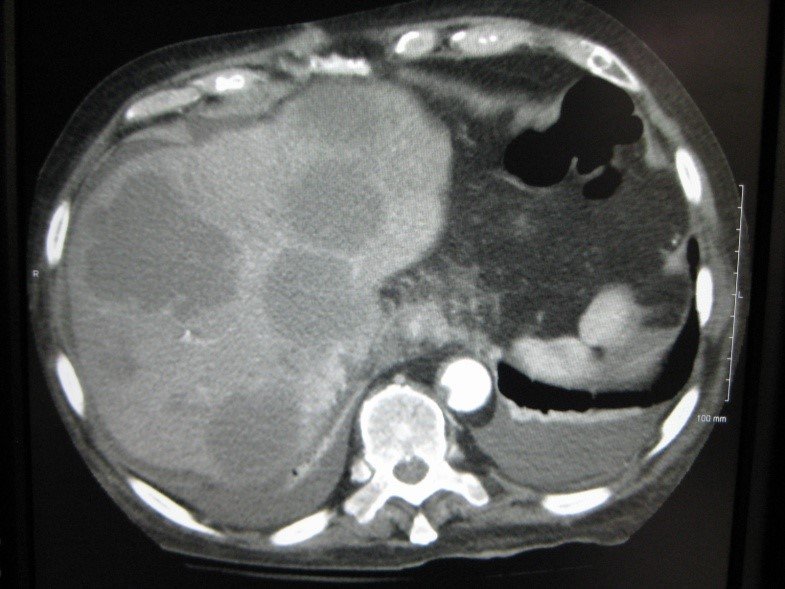

Abses diaqnozunu dəqiqləşdirmək üçün klinik əlmətlərlə yanaşı görüntüləmə və laborator müayinələr aparılmalıdır. Yerli və ümumi sepsis əlamətləri ilə yanaşı USM və ya tomoqrafiyada qaraciyərdə abses boşluğun görünməsi diaqnozu dəqiqləşdirir. Absesdə qaztörədən bakteriyalar olduqda və ya bağırsağa açılarsa içərisində qaz görünür (25%).

Diaqnostik əlamətləri:

• Sistlərdən fərqli olaraq abseslərin sərhədi kəskin olmur, möhtəviyyatının sıxlığı yüksək, hətta nekrotik toxumalar olarsa, heterogen görünür.